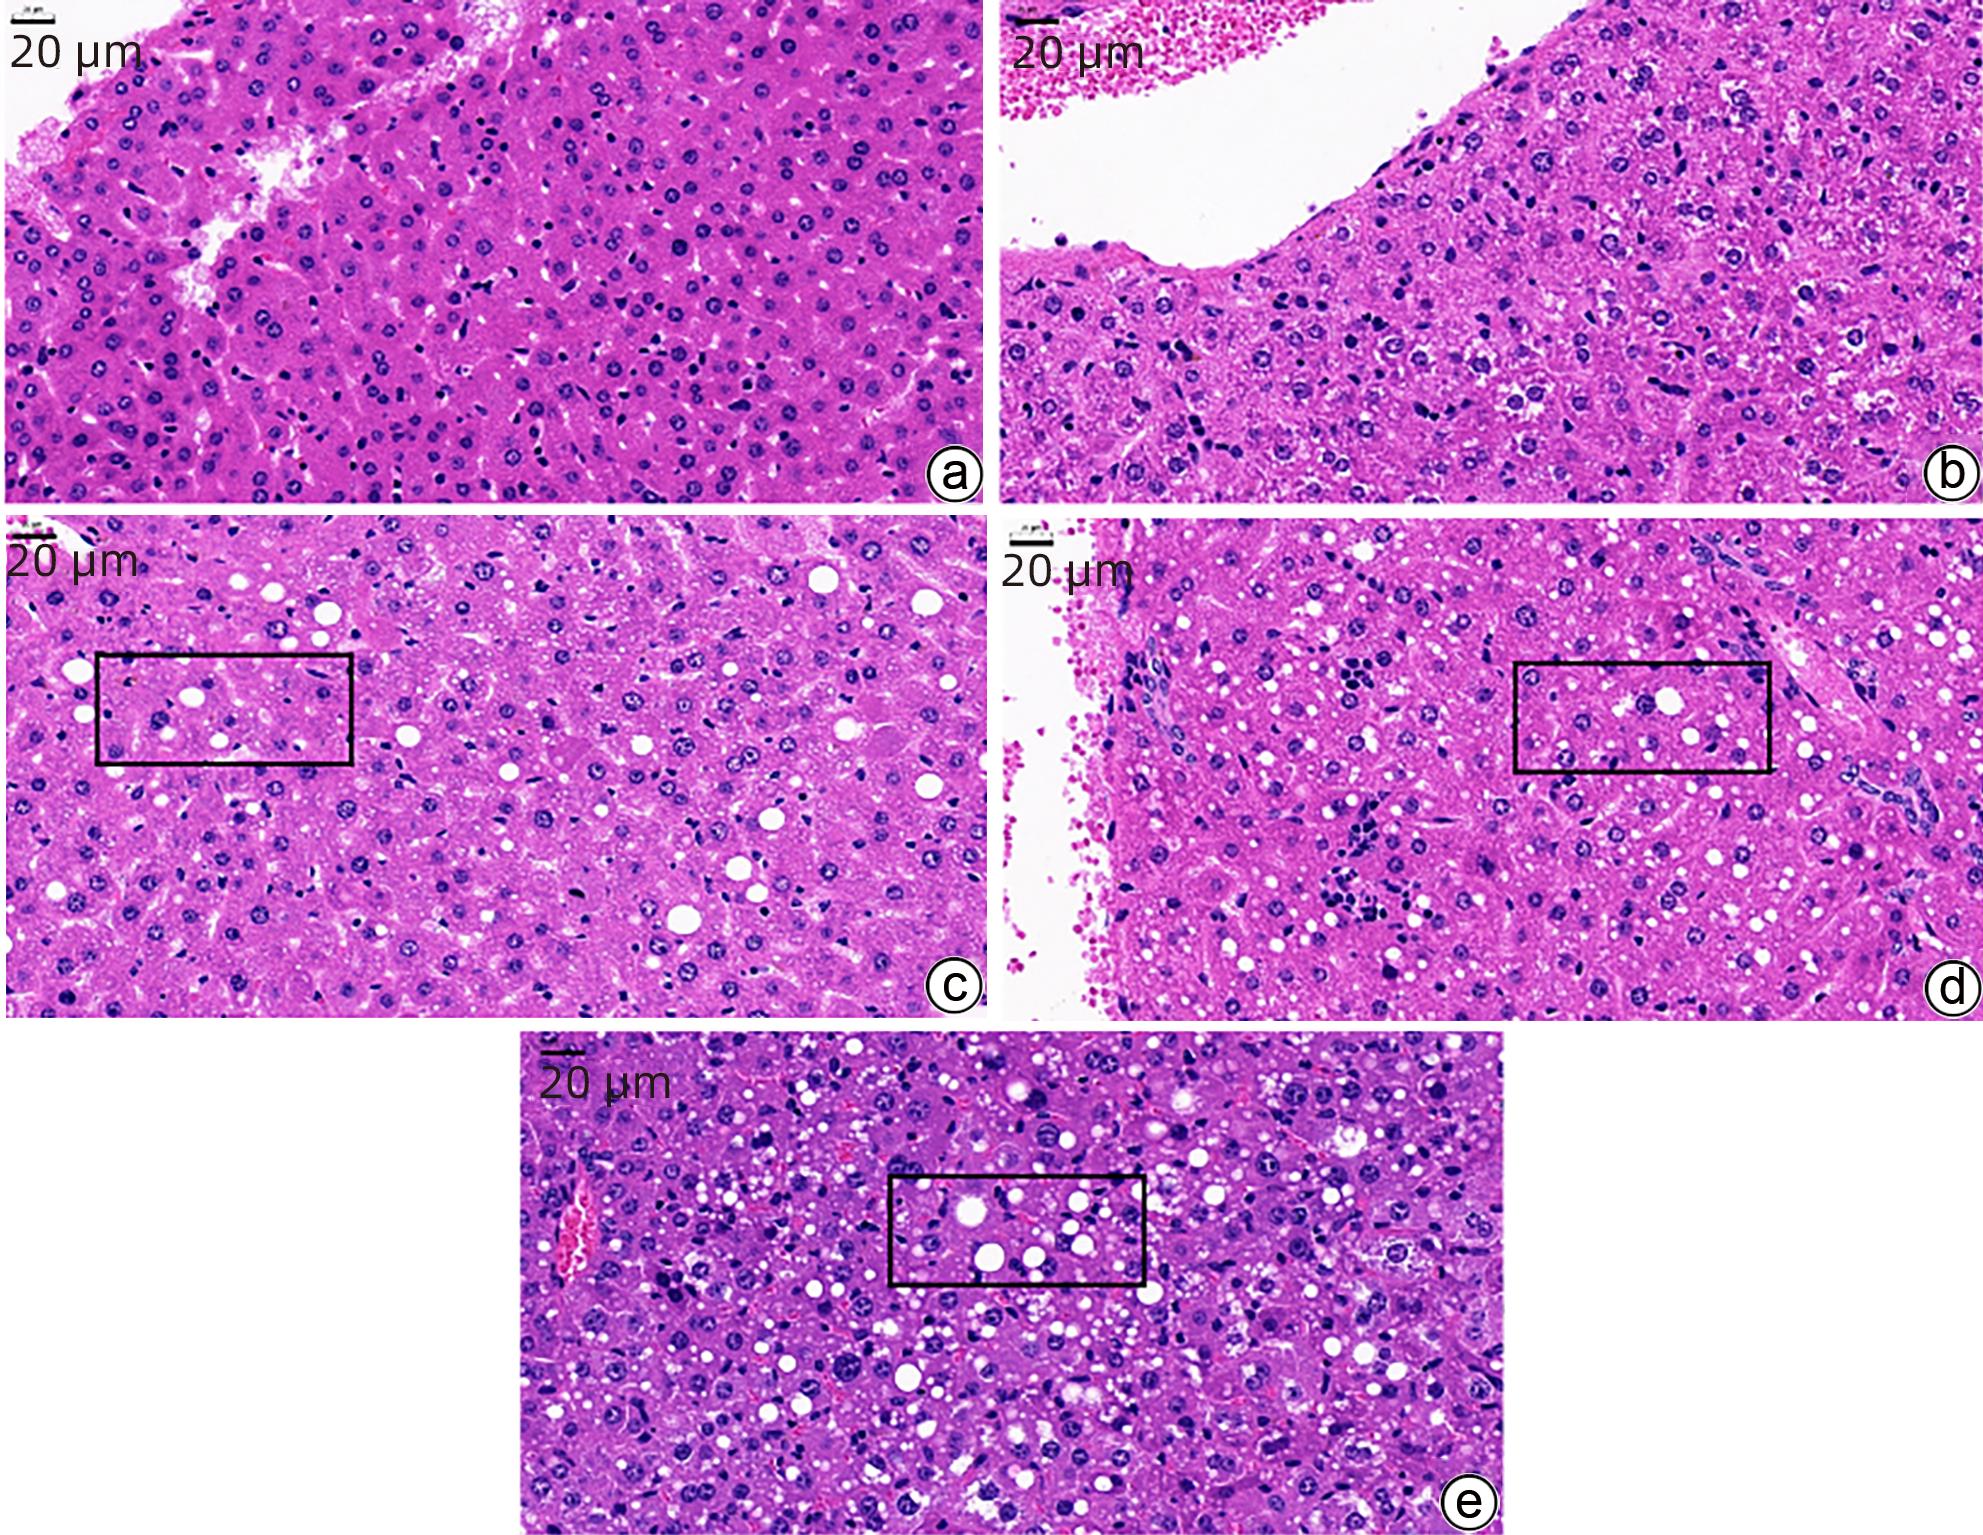

Protective effect of Genistein against nonalcoholic fatty liver disease in ovariectomized mice and its mechanism

Xiangyu ZHU, Yong JIN

2024, 40(4): 706-711. DOI: 10.12449/JCH240411

Abstract(1170) HTML (318) PDF (1690KB)(78)

Abstract:

Objective  To investigate the protective effect of Genistein against nonalcoholic fatty liver disease (NAFLD) in ovariectomized (OVX) mice and its mechanism.  Methods  A total of 40 female C57BL/6 mice, aged 6 weeks, were used to establish an OVX mouse model, and then they were randomly divided into blank group, 4-week model group, 6-week model group, 8-week model group, and 10-week model group, with 8 mice in each group. Under the same environmental conditions, the mice were given high-fat diet for modeling, and pathological examination showed that NAFLD was successfully induced by 10-week high-fat diet. Another 40 female C57BL/6 mice, aged 6 weeks, were randomly divided into blank group, sham operation group (Sham group), OVX group, OVX+L-Genistein (4 mg/kg body weight) group, and OVX+H-Genistein (8 mg/kg body weight) group. The mice in the Sham group were given the same procedure of OVX, without the ligation of the ovarian artery and the resection of the ovary. The mice in the blank group were given normal diet, and those in the other groups were given high-fat diet. Genistein was dissolved in DMSO, and the mice in the Sham group and the OVX group were treated with solvent solution alone by gavage, once a day for 10 consecutive weeks. Body weight and visceral index were recorded, and the mice were sacrificed to collect serum and liver tissue. Kits were used to measure the activity of alanine aminotransferase (ALT) and aspartate aminotransferase (AST) and the serum levels of triglyceride (TG) and total cholesterol (TC), and HE staining and oil red O staining were used to observe liver histopathology; Western blot was used to measure the protein expression levels of sterol regulatory element-binding protein 1c (SREBP-1c) and peroxisome proliferator-activated receptor alpha (PPARα) associated with lipid metabolism in liver tissue. A one-way analysis of variance was used for comparison of continuous data between multiple groups, and the Dunnett-t test was used for further comparison between two groups.  Results  After 10 weeks of high-fat diet, the OVX+L-Genistein group and the OVX+H-Genistein group had significantly lower body weight, liver index, and liver tissue weight (all P<0.05). In addition, Genistein significantly downregulated the serum levels of TC and TG (P<0.05) and reduced the activities of serum AST and ALT (P<0.05). HE and oil red O staining showed that compared with the OVX group, the OVX+L-Genistein group and the OVX+H-Genistein group had a significant reduction in the accumulation of lipid droplets. Western blot showed that after Genistein intervention, there was a significant reduction in the protein expression level of SREBP-1c and a significant increase in the protein expression level of PPARα (P<0.05).  Conclusion  Genistein exerts a protective effect against NAFLD in OVX mice possibly by regulating the expression of SREBP-1c and PPARα, thereby promoting fatty acid oxidation and inhibiting liver lipid synthesis.